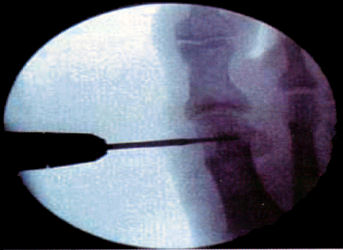

Minimal Invasive Surgery, Minimal Incision Surgery, or Pericutaneous Surgery, permits surgery in the affected area performed with a small incision.

MIS of the foot respects the joint surfaces, does not use ischemia and in general internal fixation is not required. The same pre operative indications and studies are performed as in traditional surgery, (Dr. Mariano De Prado).

MIS surgical techniques is a good valid alternative in forefoot surgery. Always the indications must be correct and the surgeon must have a good preparation and use the proper instrumentation and material needed to perform this type of surgery. (Dr. Ramon Viladot). Following the principles of Minimal Invasive Surgery we can perform the following procedures or surgical acts:

Osteotomies in the 1st metatarsal can be distal metatarsal osteotomy such as the ReverdinIsham with a medial wedge respecting the lateral cortex and performing an Osteoclasis to correct the PASA and we can also perform a modification of this osteotomy by completing it and sliding the metatarsal head laterally thereby increasing the relative closure of the 1st intermetatarsal angle. Next we can do a proximal metatarsal osteotomy performed with a wedge osteotomy proximal laterally to close the intermetatarsal angle. Another procedure that we can perform is an abductor release which is a Modified McBride. The next procedure we can do is also an osteotomy of the base of the proximal phalanx (Akin).